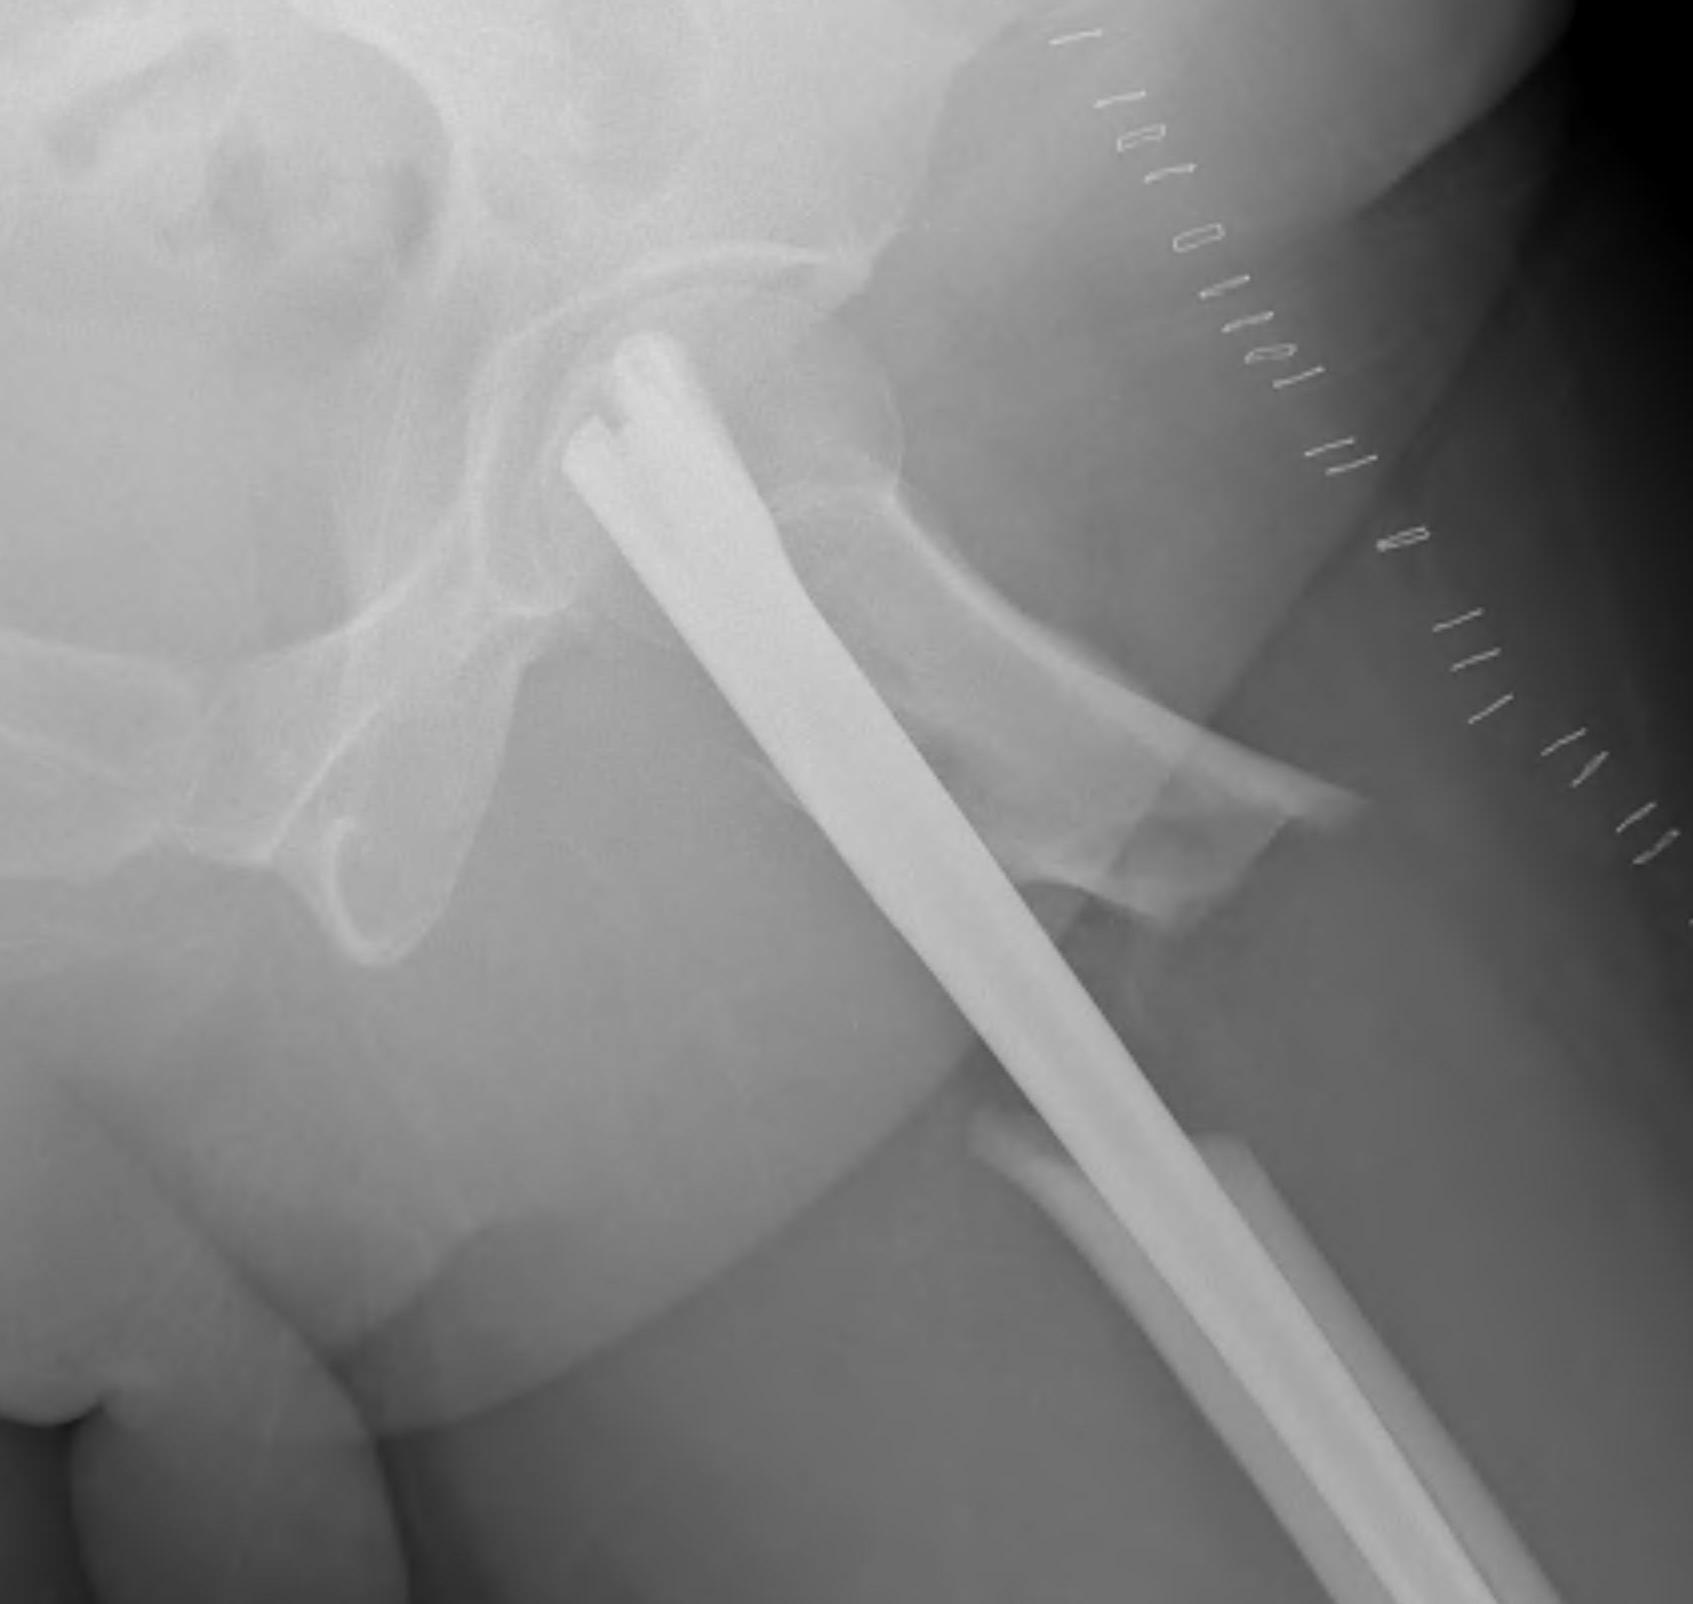

Position

Lateral

- helps reduction of distal fragment to flexed proximal fragment

- easier piriformis access

Supine on traction table

- easier imaging

- longitudinal traction

Entry point

Greater trochanteric

- simple

- need proximal fragment reduced

Piriformis

- may aid reduction, as a trochanteric nail will push proximal fragment into valgus

- more difficult to obtain